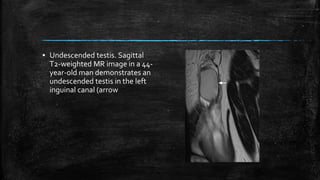

▪ Undescended testis. Sagittal

T2-weighted MR image in a 44-

year-old man demonstrates an

undescended testis in the left

inguinal canal (arrow